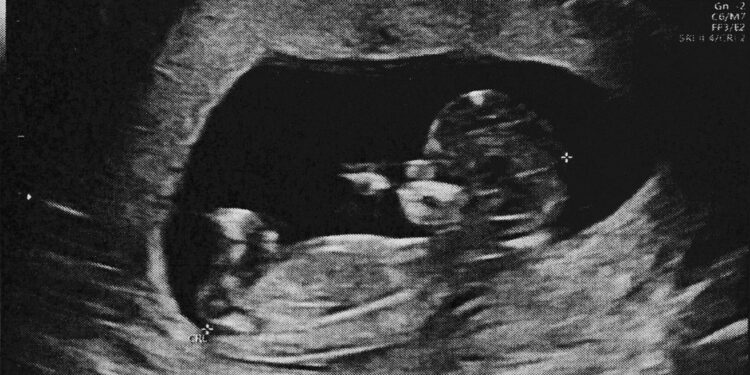

Nors dažniausiai ultragarsiniai tyrimai žinomi kaip priemonė stebėti nėštumo eigą ir matyti besivystantį vaisių, jų taikymo spektras labai platus. Tokie tyrimai padeda išsiaiškinti skausmo, patinimo ar kitų simptomų kilmę, kai reikia detaliau peržiūrėti vidaus organų būklę.

Skirtingai nei rentgeno ar kompiuterinės tomografijos tyrimai, ultragarsas ne naudoja jonizuojančiosios spinduliuotės. Tai lemia, kad šis metodas ypač tinkamas stebėti nėštumo eigą ir vertinti vaisiaus būklę įvairiais nėštumo etapais.